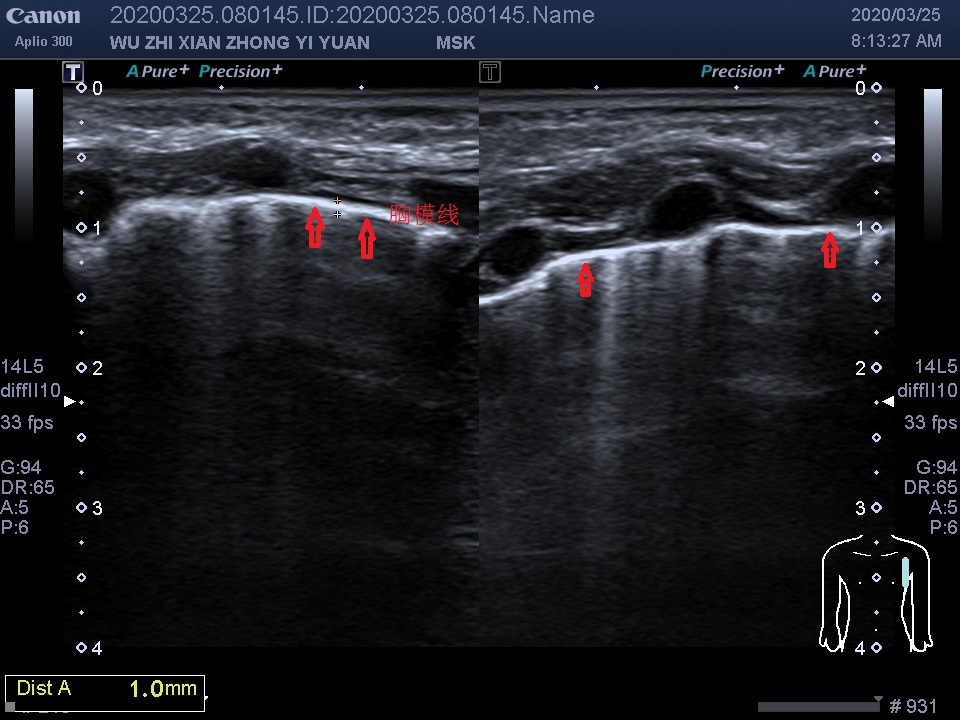

image007

上图箭头所示:可见双侧胸模线均增厚,右侧厚约1.0mm、左侧厚1.2mm。